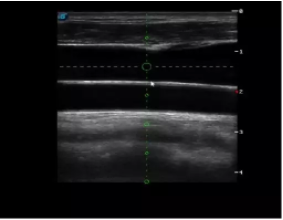

4  置管專用探頭

實(shí)時(shí)觀察穿刺針進(jìn)入血管的全過(guò)程,方便操作及較短的穿刺路徑,智能進(jìn)針尺寸提示,讓置管工作更加輕松,高效。

不同進(jìn)針路徑